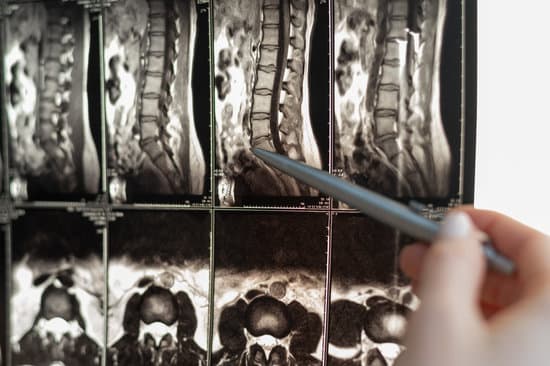

척추관 협착증을 진단하기 위해 전문의는 병력 청취 및 신체 검사를 실시하며, 필요에 따라 영상 검사를 시행합니다.

X-레이: 척추의 퇴행성 변화와 골극을 확인할 수 있습니다.

MRI(자기공명영상): 신경 압박 정도와 척추관의 상태를 정확히 확인할 수 있습니다.

CT 스캔: 척추뼈와 척추관의 구조를 세밀히 확인할 수 있습니다.